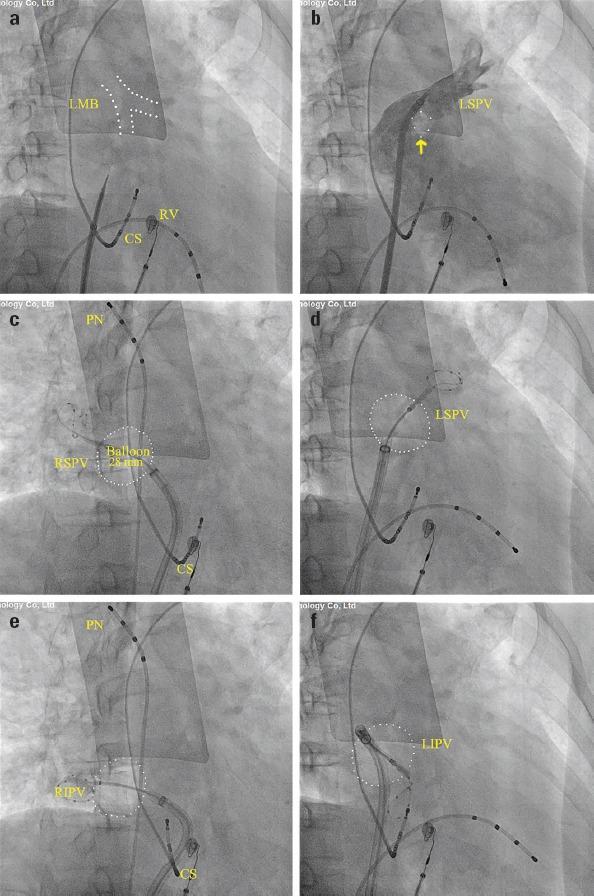

Although imaging modalities, such as transesophageal and intracardiac echocardiography, have helped to improve the safety of atrial transseptal puncture (TSP), fluoroscopy is still traditionally and widely used in TSP. The aim of the present study was to evaluate an individual knack for TSP during cryoballoon ablation of atrial fibrillation (AF) under fluoroscopy.

Through the prospective study of 72 cases of patients with paroxysmal or persistent AF admitted for cryoablation in our center, 46 cases using a puncture site toward the bifurcation of the left main bronchus (LMB group) and 26 cases using an anterior-inferior puncture site (AI group) were included in the study. The acute pulmonary vein (PV) isolation success rate, single-procedure success rate, and time-to-effect (TTE) between the two groups were analyzed.

All PVs were identified and successfully isolated, and there are no differences in the two groups. However, the mean TTE was shorter in the LMB group than in the AI group. Moreover, a higher single-procedure success rate was observed in the LMB group.

The bifurcation of the LMB can be clearly evaluated in each patient under fluoroscopy and is an anatomical landmark for the location of the left PV. TSP guided by the LMB is a new practical method for choosing individualized transseptal sites for catheter ablation of AF, which can help to shorten TTE and procedure time.